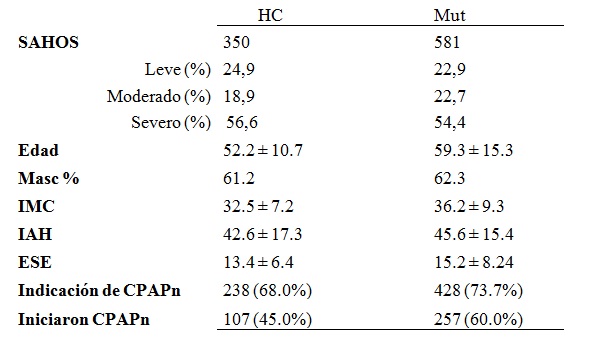

F. Tratamiento con CPAP nasal

La aplicación de presión positiva a través de la nariz (CPAPn), es el principal tratamiento disponible para el SAHOS, por lo que se muestran los resultados de la indicación de que se realizó siguiendo un algoritmo presentado previamente17. En el período 1998-2010, se realizó un relevamiento mediante seguimiento clínico o entrevista telefónica, de adherencia al tratamiento y de la forma de acceso a CPAPn. Se revisaron 1204 pacientes estudiados con PSG o PGR, de los cuales 931 fueron diagnosticados con SAHOS. Se indicó CPAPn a 666 pacientes según los criterios: IAH mayor de 30 ó IAH entre 15 y 30 asociado a síntomas severos o co-morbilidad significativa (Tabla 10).

Tabla 10. Características de los pacientes seguidos para investigar la adherencia a CPAPn. HC: pacientes del Hospital de Clínicas. Mut: pacientes del sistema mutual.

Comenzaron el tratamiento con CPAPn el 45% de los pacientes del Hospital de Clínicas y el 60% de los pacientes del área mutual. La forma de acceso al tratamiento fue: sin costo (empleados con aporte a la seguridad social); con costo parcial (seguros de salud y cajas de auxilio) y con costo completo a cargo del paciente. La imposibilidad de acceder al equipo por restricción económica no constituyó el mayor obstáculo para el comienzo del tratamiento (16,4% y 4,7%). El resto de los pacientes que no comenzó el tratamiento, pertenece a un grupo denominado “rechazo inicial del tratamiento” cuya tasa fue de 38,7% y 35,3%. (Figura 13).

Para identificar los factores asociados al rechazo inicial del tratamiento se realizó un estudio con diseño caso-control anidado. Los resultados se presentan en la Tabla 11. Se identificaron los siguientes factores asociados con el rechazo inicial: somnolencia leve (ESE < 10), grado leve o moderado (IAH < 30), eventos adversos, sin educación secundaria y ausencia de actividad laboral.